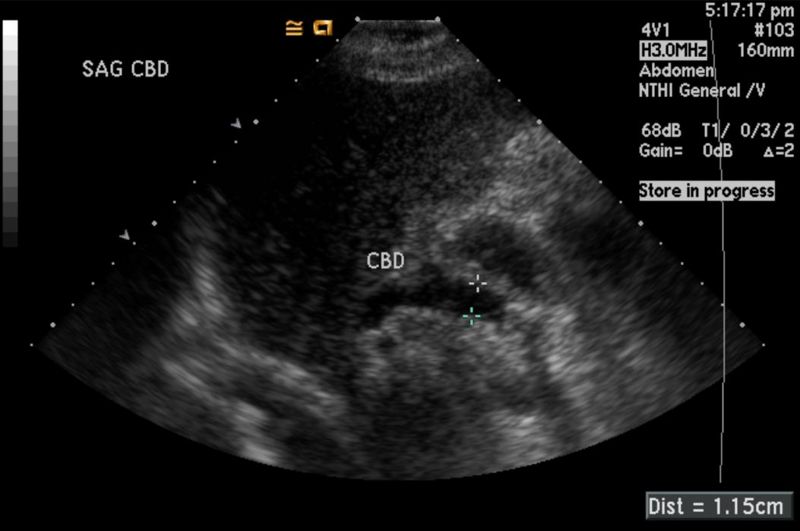

El ultrasonido mamario utiliza ondas sonoras para generar imágenes del tejido mamario en tiempo real, sin emplear radiación. Este estudio es especialmente útil para diferenciar entre masas sólidas y quísticas, identificar lesiones que no son visibles en la mastografía y evaluar áreas específicas que el médico considera sospechosas.

Cuando la mastografía muestra hallazgos dudosos, el ultrasonido puede proporcionar información adicional que ayuda a caracterizar mejor las lesiones y decidir si es necesario realizar una biopsia u otro procedimiento.